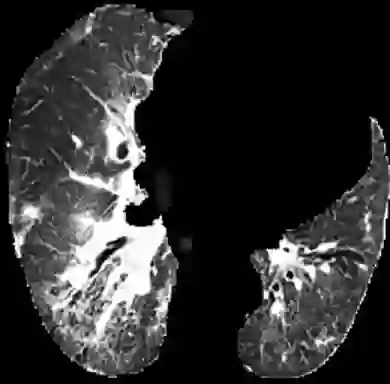

In the field of medical imaging, particularly in tasks related to early disease detection and prognosis, understanding the reasoning behind AI model predictions is imperative for assessing their reliability. Conventional explanation methods encounter challenges in identifying decisive features in medical image classifications, especially when discriminative features are subtle or not immediately evident. To address this limitation, we propose an agent model capable of generating counterfactual images that prompt different decisions when plugged into a black box model. By employing this agent model, we can uncover influential image patterns that impact the black model's final predictions. Through our methodology, we efficiently identify features that influence decisions of the deep black box. We validated our approach in the rigorous domain of medical prognosis tasks, showcasing its efficacy and potential to enhance the reliability of deep learning models in medical image classification compared to existing interpretation methods. The code will be publicly available at https://github.com/ayanglab/DiffExplainer.